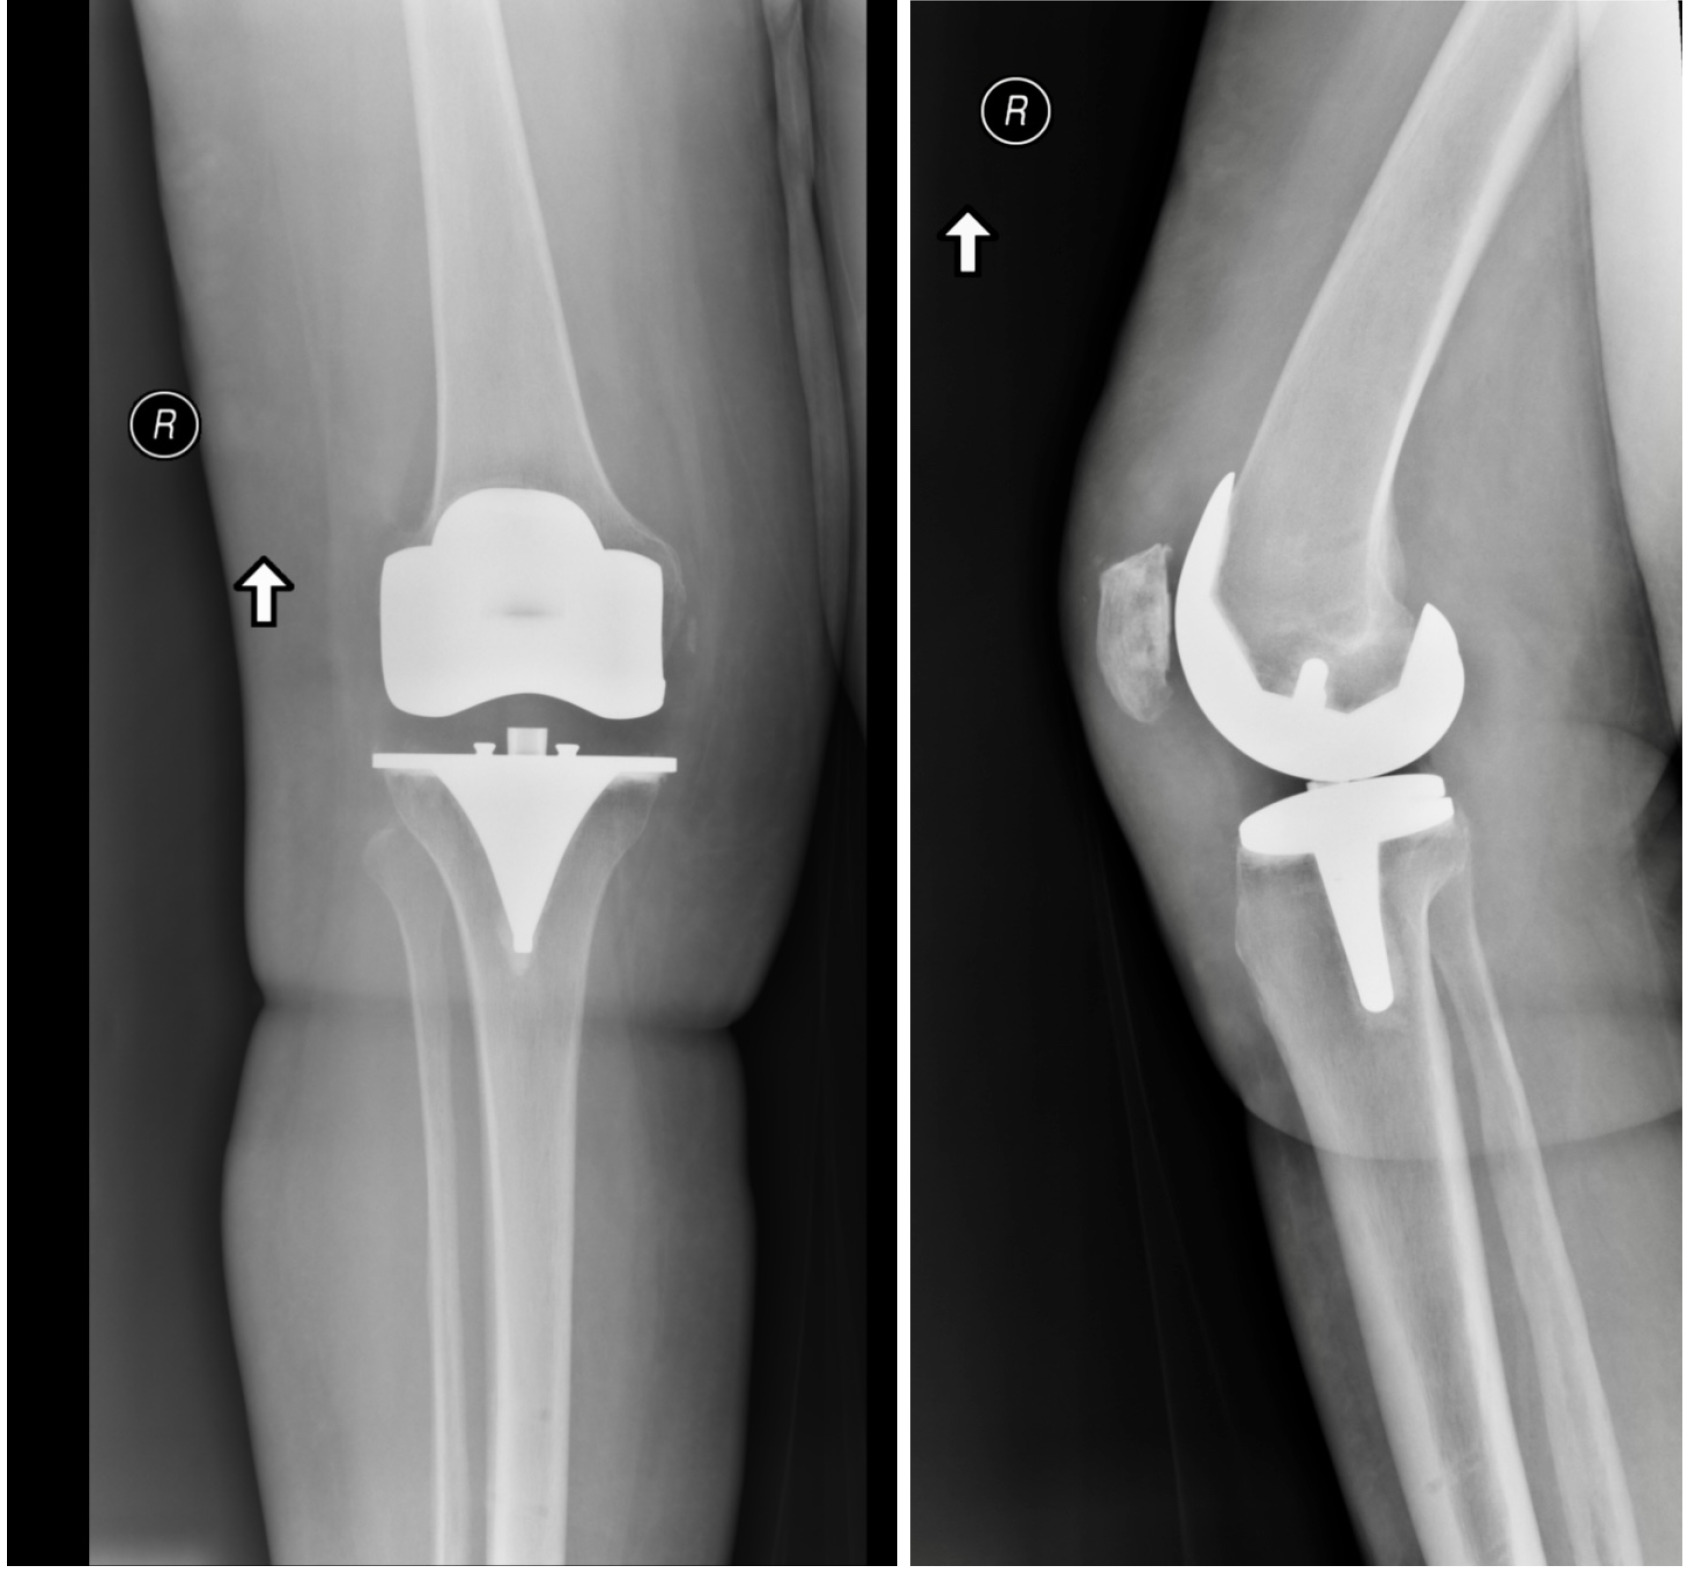

Once the plan was finalized, bone cuts were made and a size 3 tibia, 12 mm ultra-congruent poly, size 3+ femur, and 29 x 8 patella were trialed. Final assessment showed 2-degree valgus alignment and a range of motion 0-141 degrees with excellent stability throughout. Final prostheses were cemented using standard technique and a final range of motion showed 0-141 degrees without any external pressure (Figure 5). The wound was closed in standard fashion and patient was discharged to recovery in stable condition.